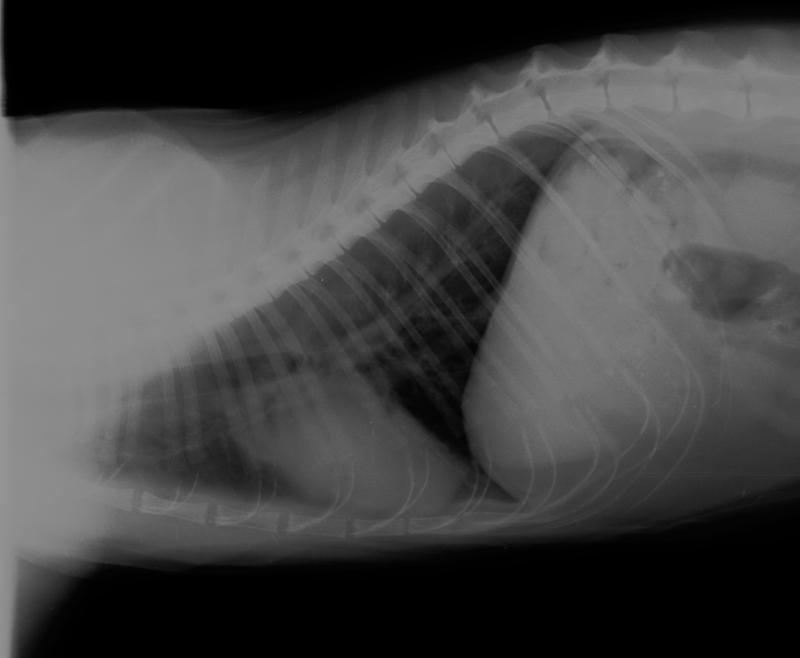

Katze Wasser In Der Lunge Captions More

Katze Wasser In Der Lunge Captions More from captionsmorenyc.blogspot.com